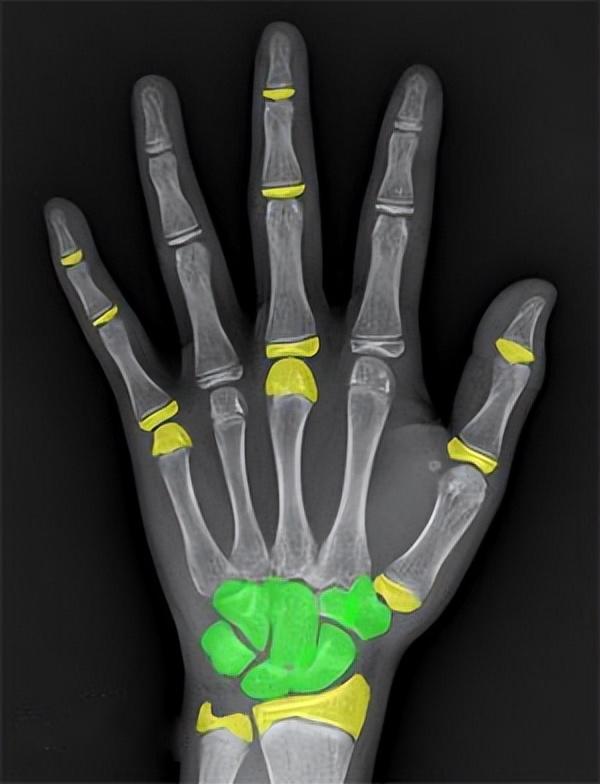

通常,骨龄检测需要拍摄左手手腕部位的X光片,观察左手掌指骨、腕骨及桡尺骨下端的骨化中心的发育情况,从而确定骨龄。